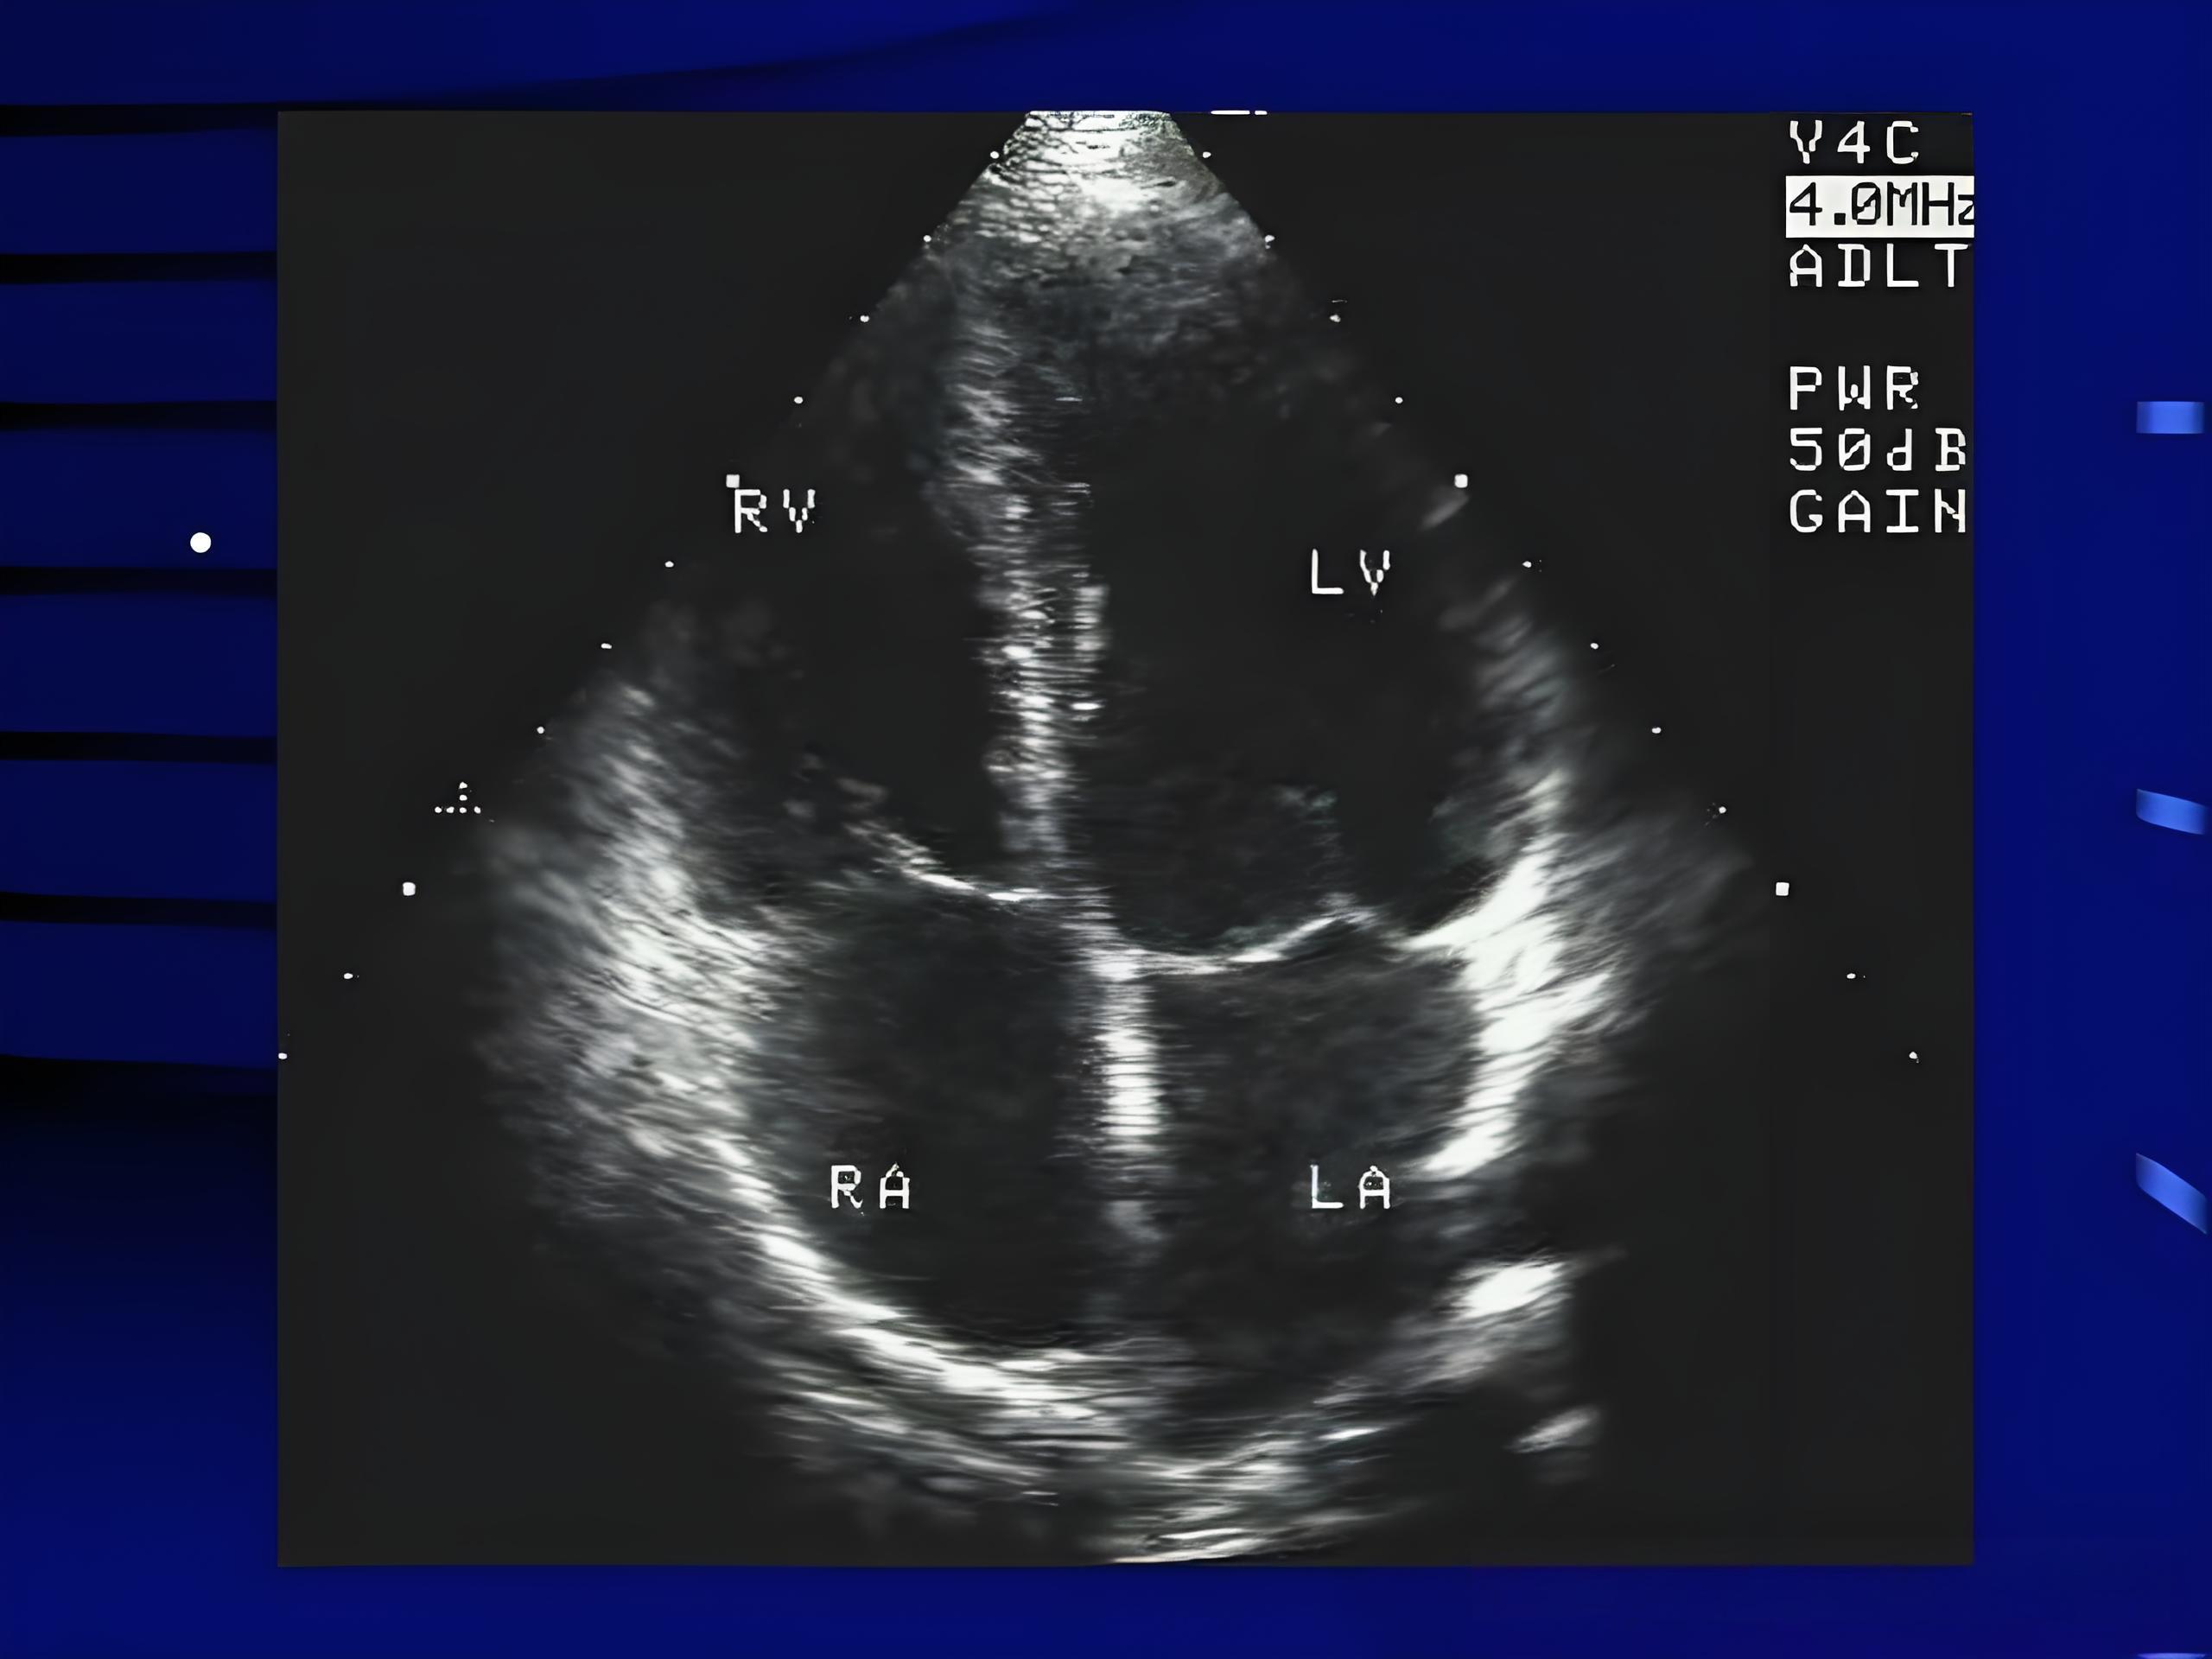

3. 心脏彩超(超声心动图)——给心脏拍个“写真”

原理:用超声波看看心脏结构和泵血功能。

优点:无创、无辐射,孕妇都能做。

缺点:看不到血管内部堵没堵,只能看“房子”有没有塌,不能看“水管”有没有堵。